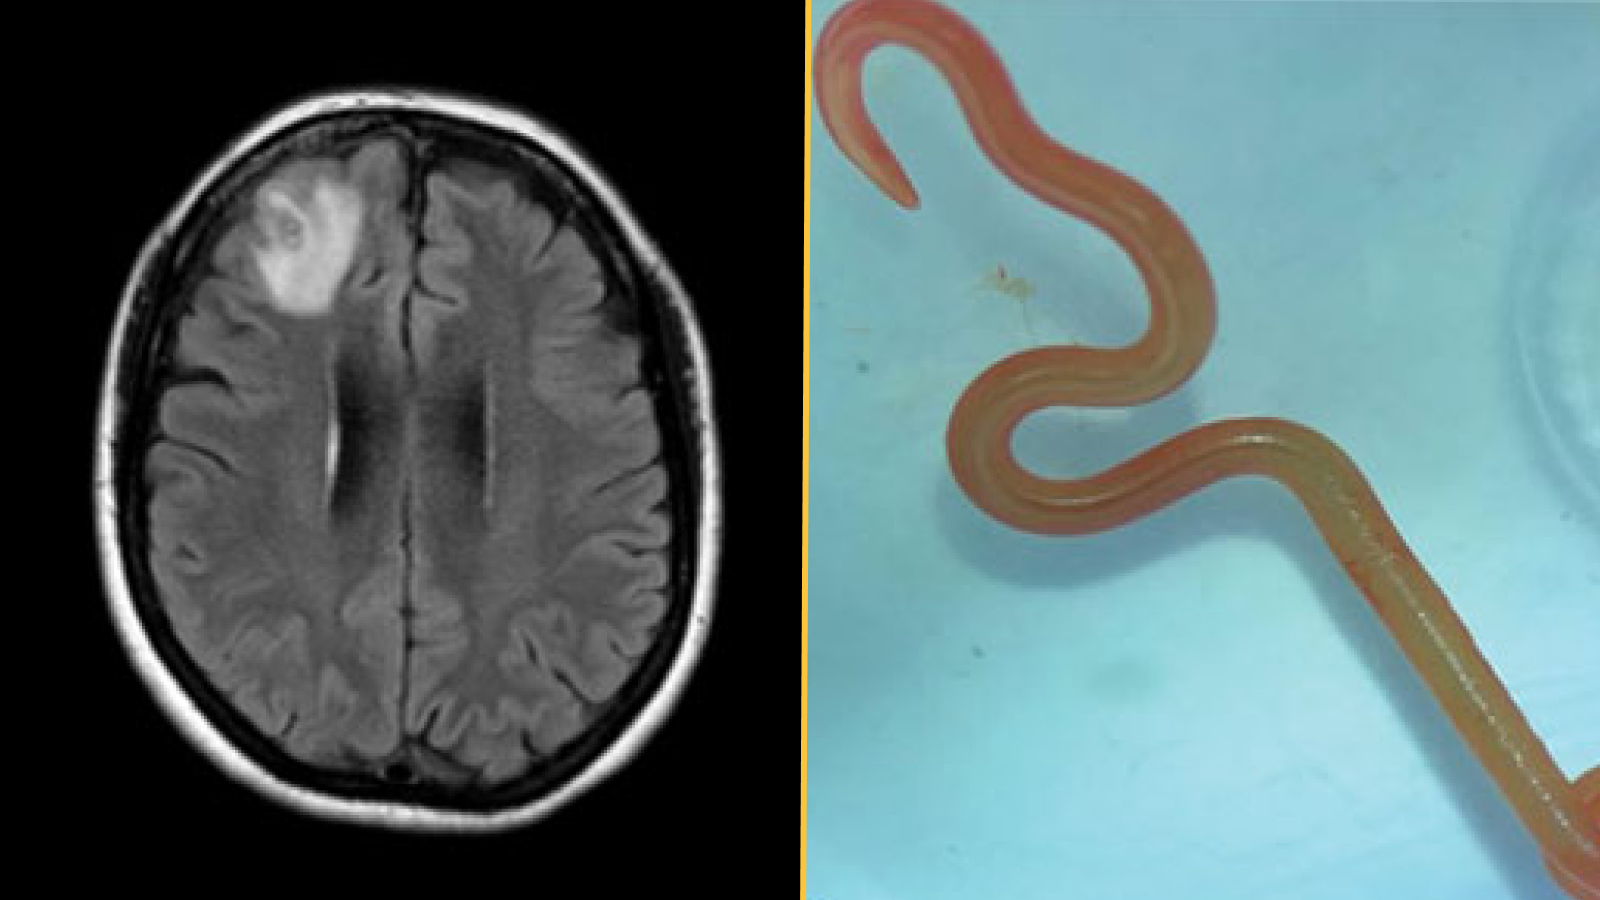

Le diagnostic : Environ un an après sa première visite à l’hôpital, la femme a commencé à développer des signes de dépression et à avoir des épisodes d’oubli. Les médecins ont ordonné une IRM de son cerveau et ont détecté une lésion sur le lobe frontal droit. Ils ont ensuite réalisé une biopsie ouverte pour exposer et examiner la zone endommagée. C’est à ce moment-là qu’ils ont découvert « une structure en forme de fil » à l’intérieur de la lésion, qu’ils ont identifiée comme étant un ver parasite vivant appelé helminthe, selon un rapport de son cas.

Le ver était rouge vif et mesurait environ 3 pouces (80 millimètres) de long et 0,04 pouces (1 millimètre) d’épaisseur.

Ce qui rend le cas unique : Les médecins ont identifié l’helminthe comme une larve de troisième stade de Ophidascaris robertsiun type de nématode parasite originaire d’Australie. Les vers adultes se reproduisent à l’intérieur des pythons des tapis (Morelia spilota), mais le nématode peut infecter d’autres animaux au cours des stades larvaires de son cycle de vie.